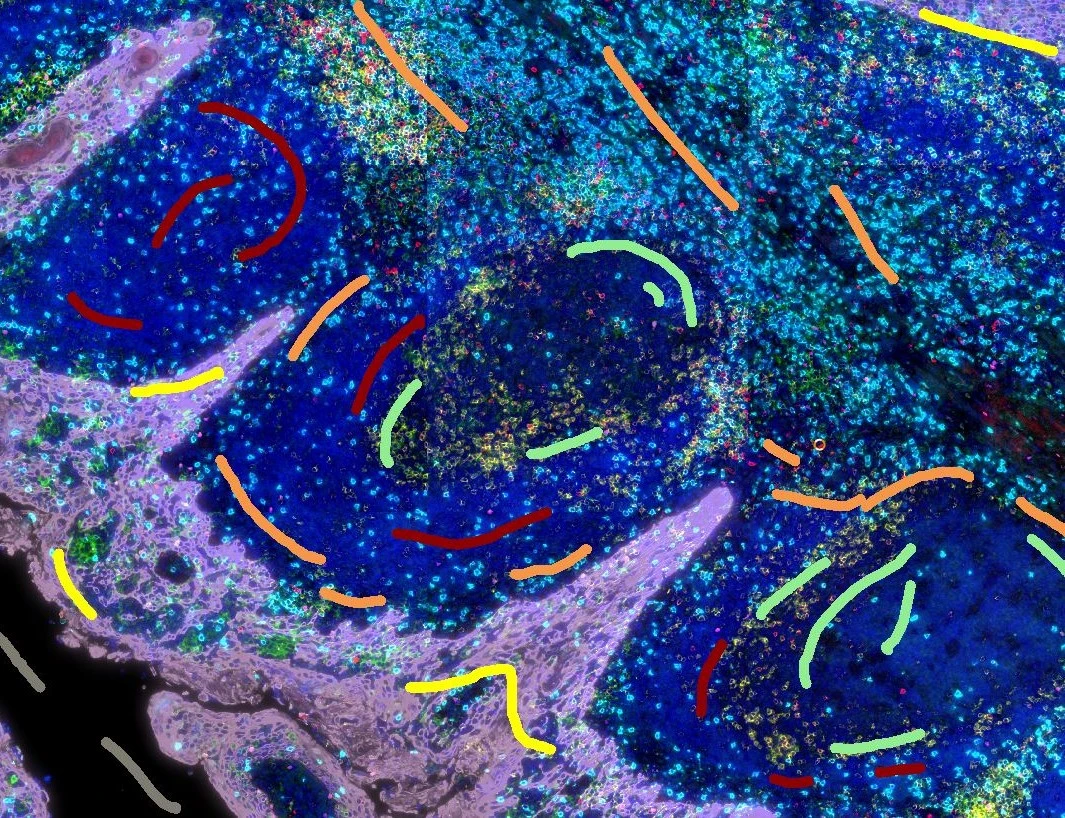

IF Swiss Roll

The IF Swiss Roll App segments tissue into subclasses (e.g., mucosa, follicles, connective tissue), detects nuclei, and identifies phenotypes via IF stains.

mouse, colon, fluorescence, immune cell follicles

The IF Swiss Roll App allows for detection of the swiss roll, and the segmentation into different subclasses (mucosa, immune cell follicles, connective tissue, background). Further it detects nuclei and identifies phenotypes based on specific IF stains. The App outputs area (µm2) of detected tissues/tissue classes, count of total cells as well as in each detected area. Count and % of specific phenotype detected in total as well as in the tissue classes.

Tissue classification

Nuclei and Phenotype detection